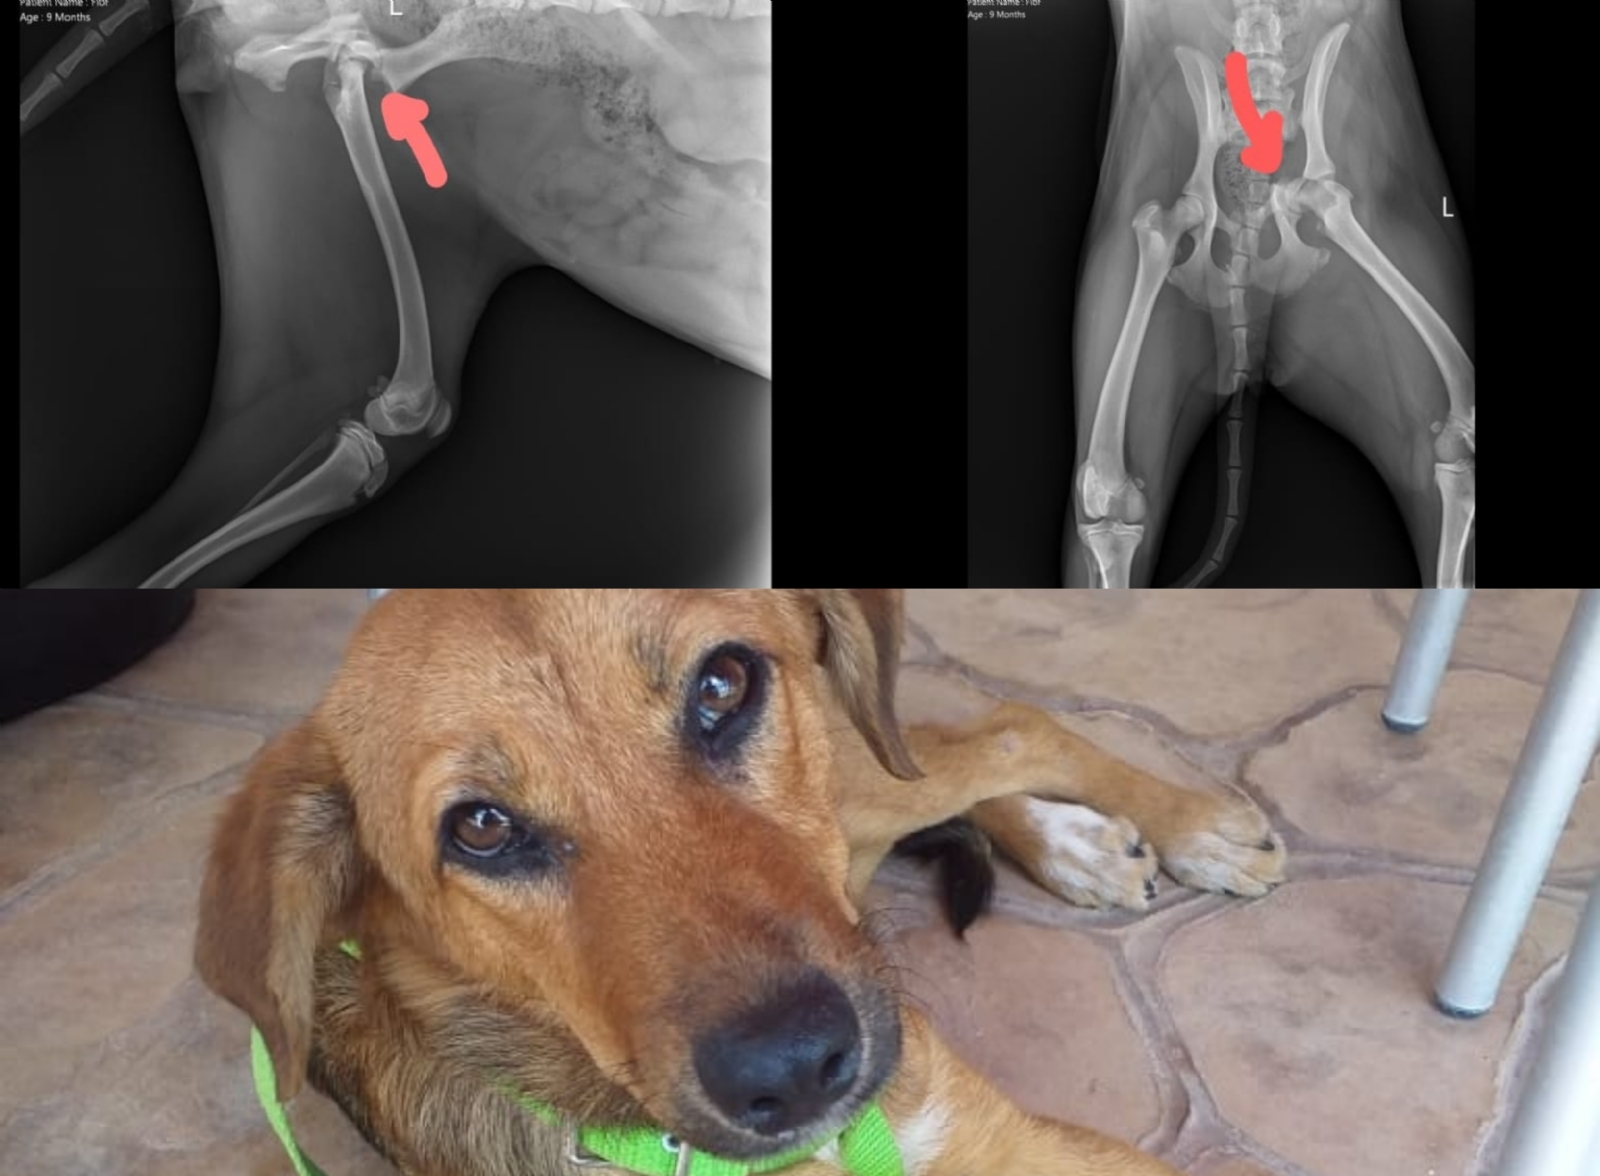

Una usuaria de redes sociales pidió ayuda a los internautas para la operación de una perrita que tiene una fractura de cadera.

A través de su cuenta de Facebook Jaki Tzuc pidió ayuda a los internautas para conseguir fondos y operar a una perrita que resultó con una fractura de cadera tras ser atropellada por un conductor.

Después de llevarla al veterinario y evaluarla se determinó que la perrita necesita una operación para corregir una fractura de cadera misma que tiene un valor de 10 mil pesos, debido a que la familia no cuenta con los recursos decidieron pedirle ayuda a los internautas.